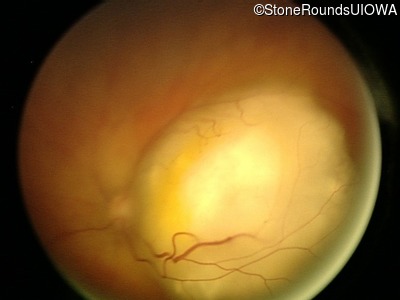

Fundus Photography - Right - CSM

Exemplar